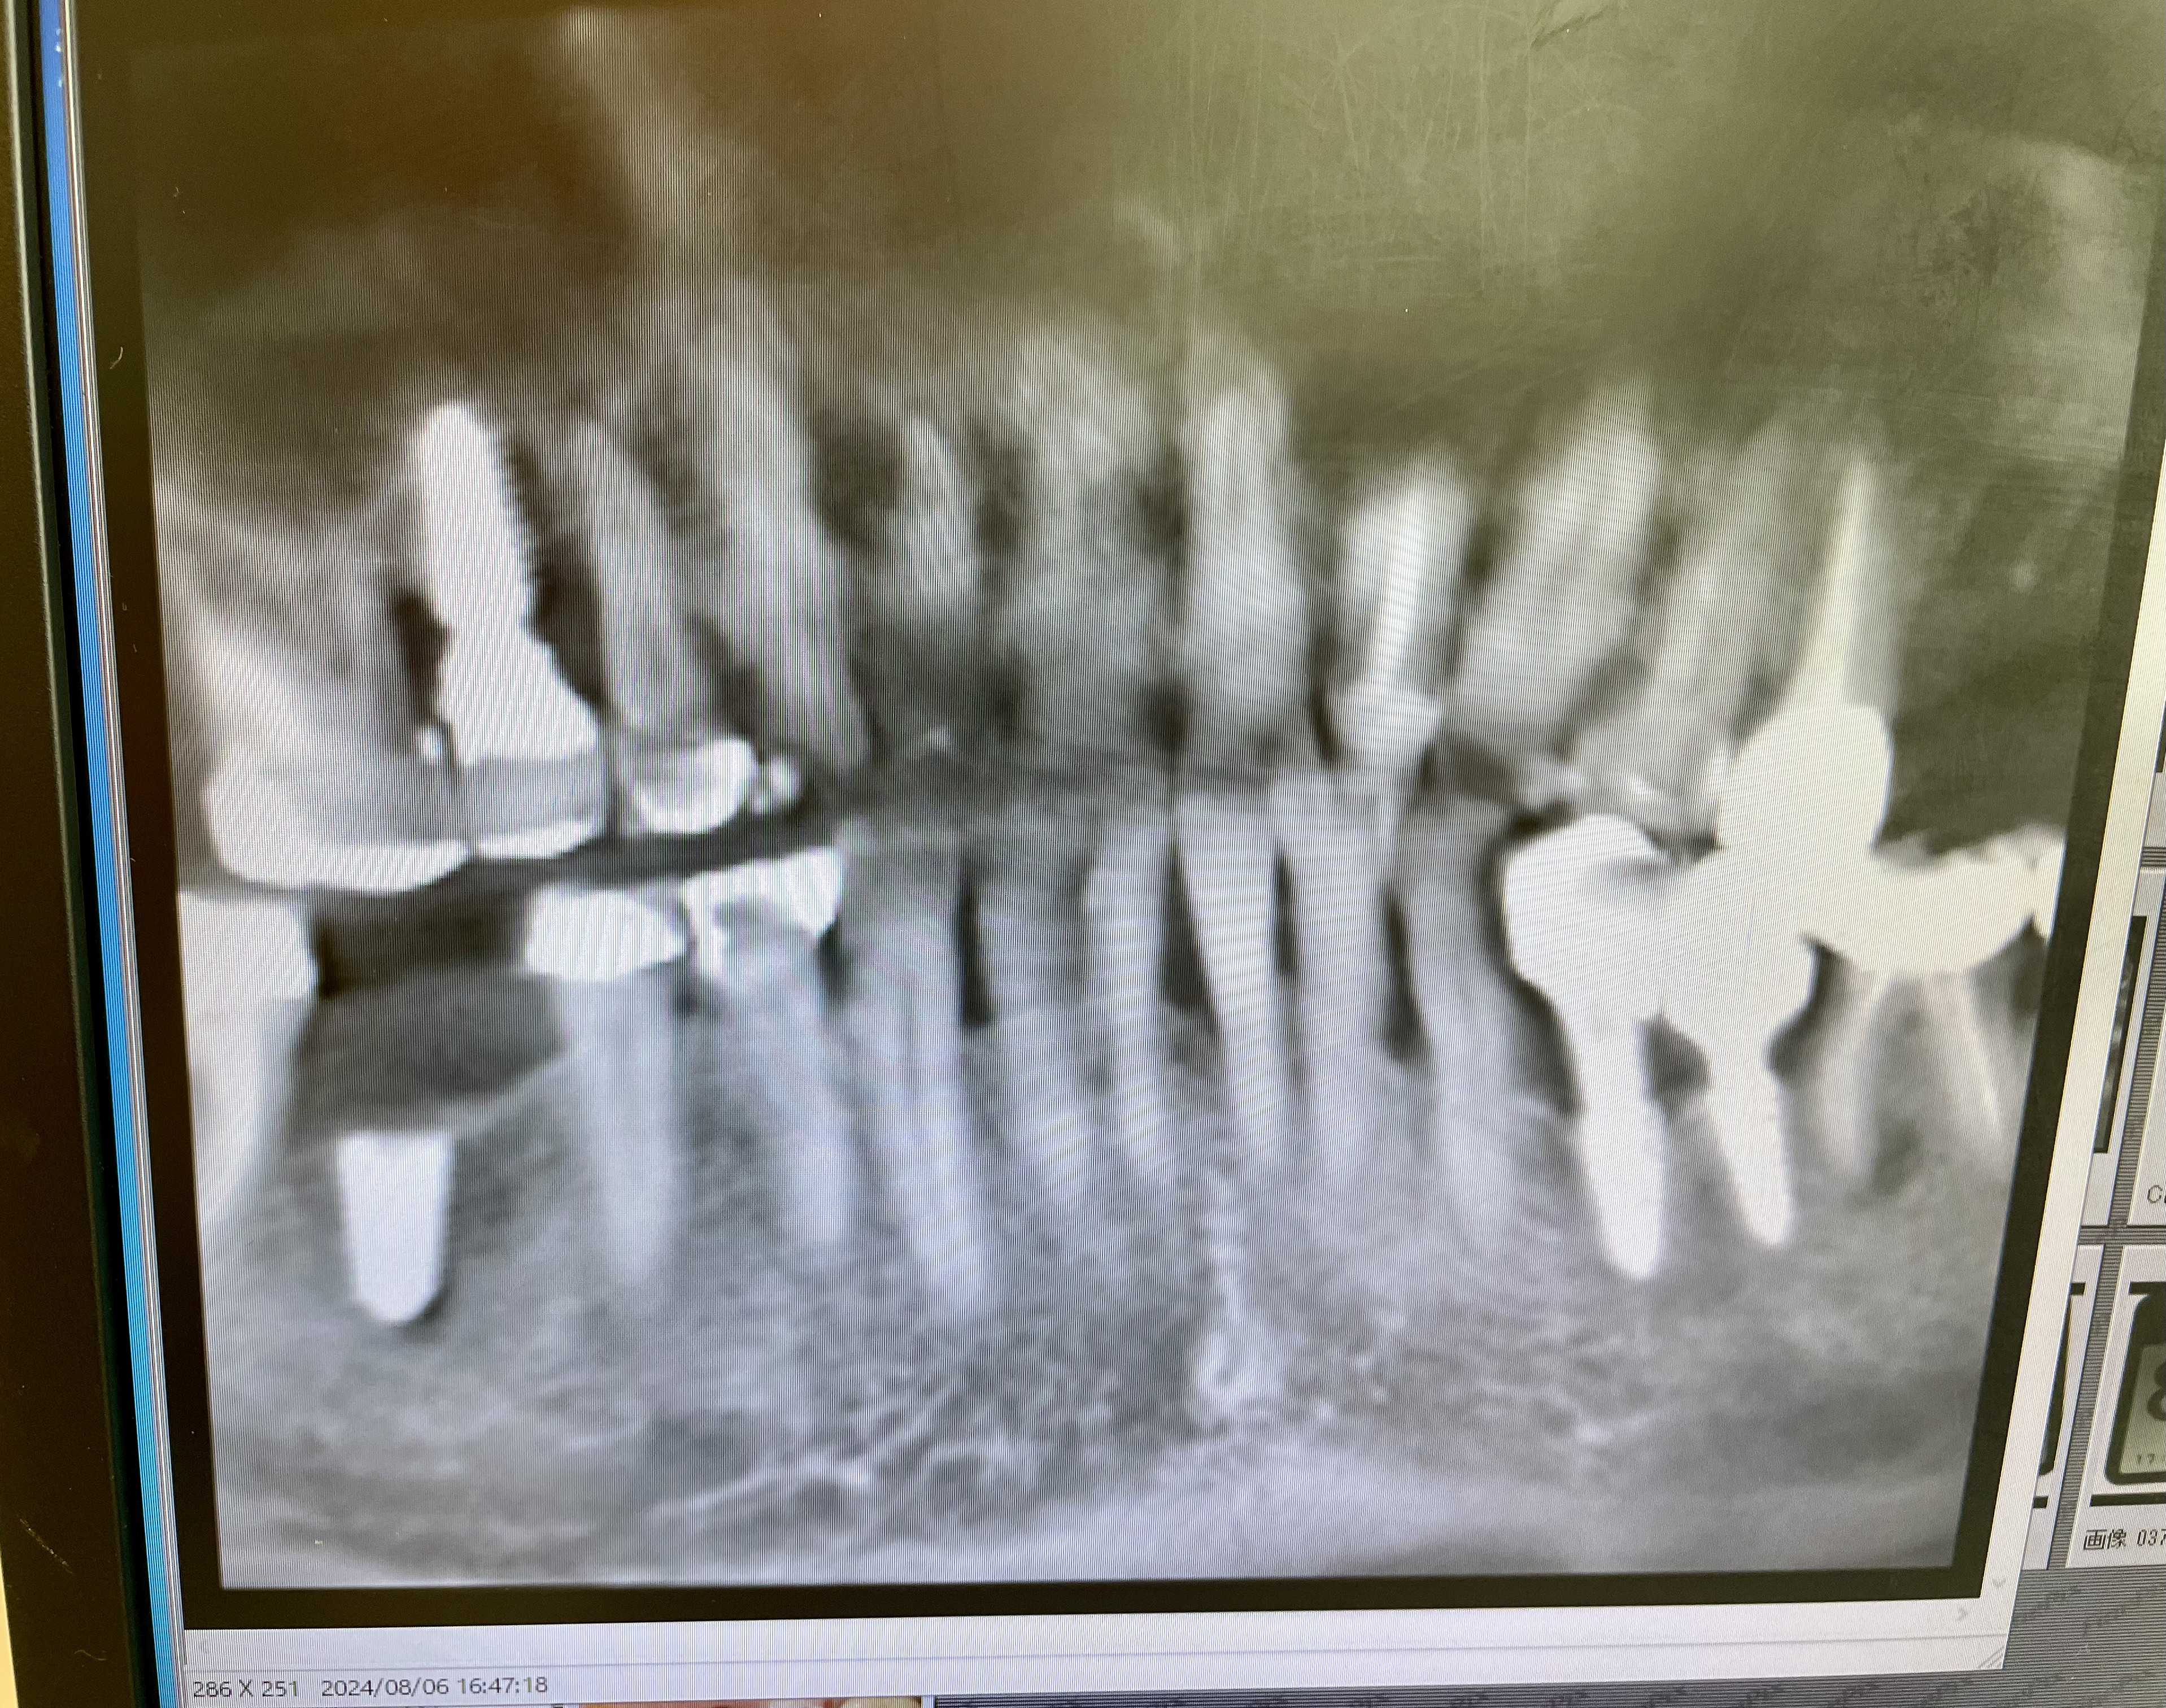

Only days after the extraction of two molars I return to the chair. This time it is an operation to screw in another implant. It is not much fun but better than being outside.